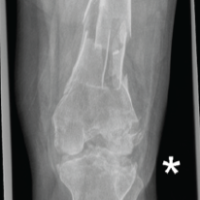

Figure 3: Intraoperative fluoroscopic images illustrating osteotomy and fixation stages. (a) Lateral view after completion of biplanar tibial tuberosity osteotomy, before graft placement and fixation; (b) Anteroposterior view after osteotomy, showing gap created for graft insertion; (c) Anteroposterior view following final implant fixation with tricortical graft in place; (d) Lateral view following dual-pillar plate fixation and tibial tuberosity screw placement.

Fig. 3 shows intraoperative fluoroscopic images demonstrating the osteotomy site (Fig. 3a and b) and the subsequent fixation with a locking plate and screws after deformity correction (Fig. 3c and d). These images illustrate the stepwise execution of the osteotomy and stabilization.